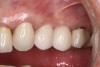

(26.) Postoperative individual implant restorations on Nos. 6 through 10.

Figure 26

A 42-year-old man presented with a very loose bridge on Nos. 6 through 9 with periodontally compromised retainers on Nos. 6 and 9 (Figure 17 through Figure 19), and endodontically involved No. 10 with a calcified canal. Teeth Nos. 6, 9, and 10 were extracted, the sockets fully debrided, and pontic soft tissue on Nos. 7 and 8 sculpted to be symmetrical in soft tissue contour with the contralateral lateral incisor and central incisor locations. Implants were secured in position Nos. 6 through 10 (Figure 20) in excess of 45 Ncm, the bone was milled to provide unimpeded seating of temporary abutments, and temporary crowns were fabricated chairside and adjusted to be out of occlusion in centric relation and all excursions. The temporary crowns were cemented after extrusion of excess cement extraorally and the patient was prescribed antibiotics, analgesics, and instructed in postoperative care particular to immediately provisionally restored implants. At 6 months, integration was confirmed (Figure 20 through Figure 23) and after placement of scanning abutments, the implants and soft tissues were scanned. Final crowns were fabricated from the scanned images and were cemented after extrusion of excess cement extraorally (Figure 24 through Figure 26), and oral hygiene procedures were reviewed.